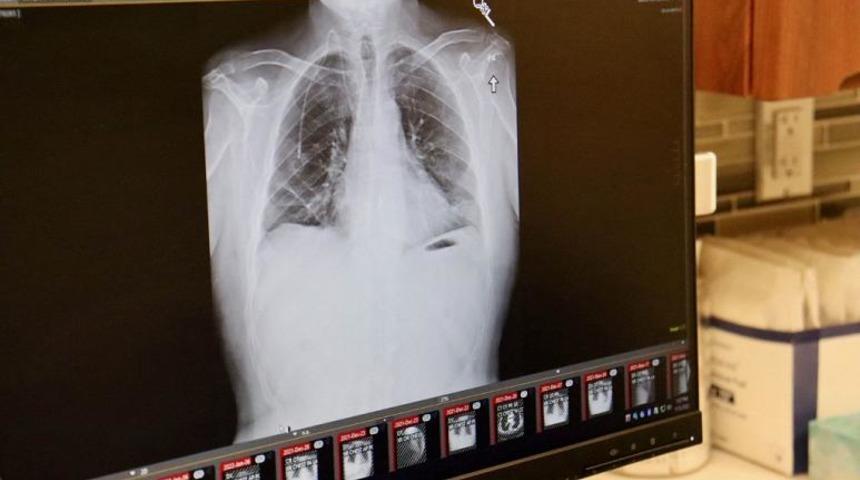

“Radyoloji Olgu Raporları” (Radiology Case Report) adlı dergide yayınlanan araştırmaya göre ismi açıklanmayan genç adamın mastürbasyon yaparken akciğerini yırttığı kayıtlara geçti. Genç adamın öksürük ve göğüs ağrısı şikayetiyle hastanenin acil servisine başvurması üzerine yapılan tetkikler sonucunda akciğerindeki yırtık tespit edildi.

20’li yaşlarında gençlerde daha önce buna benzer bir yaralanmanın görülmediği ve bunun için sert bir şekilde kusma veya ciddi fiziksel egzersiz olması gerektiğini düşünen doktorların, yaptıkları incelemede gencin ilk göğüs ağrısını mastürbasyon yaparken hissettiği kaydedildi. Doktorlar, yine cinsel ilişki sırasında ciğerin hasar görmesiyle ilgili diğer vakaları da kıyasladıktan sonra, gencin mastürbasyon yapması sonucu ciğerindeki yırtığın oluştuğu sonucuna vardı. Akciğerindeki yırtığın genç için hayati tehlikesi olmadığını belirten doktorlar bir süre daha göğüs ağrılarını yaşanabileceğini söyledi.